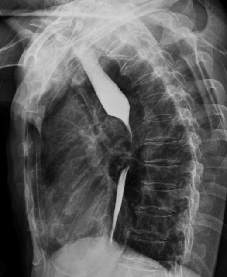

“堵”,即栓塞术,指将导管插到肿瘤的营养动脉内后,通过导管注入栓塞剂(碘油、明胶海绵等)栓塞供养肿瘤的动脉,切断肿瘤生长的营养来源。其主要原理是阻塞靶血管使肿瘤造成缺血坏死;阻塞或破坏异常血管床、腔隙和通道,使血流动力学恢复正常;阻塞血管使之远端压力下降或直径封堵破裂的血管以利于肿瘤破裂出血时止血。

该疗法在临床上最常应用于一些富血供肿瘤、恶性实体肿瘤如肝癌、肺癌等,尤其对于不能手术切除的肿瘤,血管栓塞治疗可以在一定程度上控制肿瘤,有时还能让肿瘤缩小到能手术的范畴,争取手术机会。还常常用于肿瘤侵犯或破裂引起的出血,如宫颈癌、鼻咽癌、肝癌、膀胱癌大出血等的栓塞止血治疗。此外,对于少数良性富血供肿瘤,如子宫肌瘤、子宫腺肌症、肝血管瘤等可通过栓塞达到肿瘤完全消失或明显缩小,并且有相对长的稳定时期。